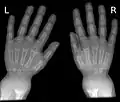

La radiologie confirme le diagnostic, et il est inutile de les multiplier. Le défaut de minéralisation des os longs s'observe particulièrement sur les radiographies de face d'un poignet et des genoux : retard ou irrégularités des points d'ossifications attendus pour l'âge (maturation squelettique), lignes métaphysaires irrégulières donnant un aspect « en toit de pagode », la corticale de la diaphyse est amincie, la densité osseuse est diminuée donnant un aspect vermoulu. Les os longs s'incurvent.

Radiographie de mains et poignets.